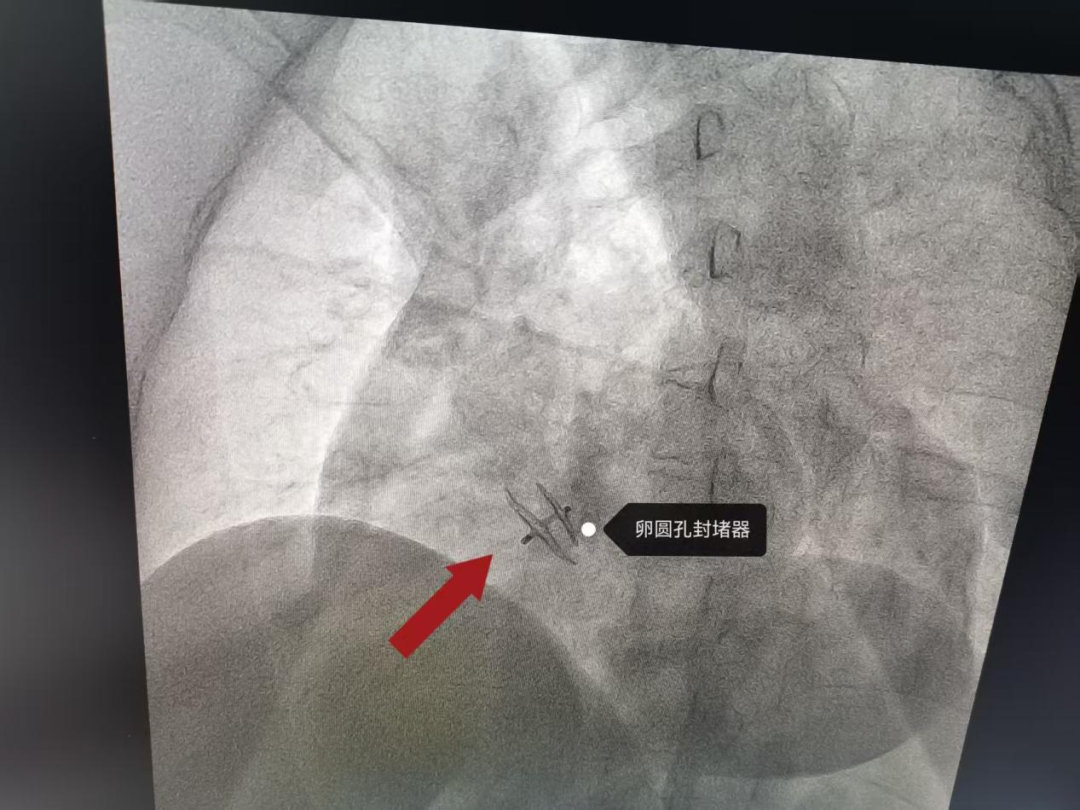

近日,丹凤县医院心血管内科团队在第四军医大学西京医院李同斌、文亮教授的悉心指导和大力协助下,成功完成首例卵圆孔未闭(PFO)介入封堵术,术后患者恢复良好,效果显著。

9月8日,在丹凤县医院心血管内科介入团队与西京医院专家的协同配合下,为患者实施经导管卵圆孔未闭封堵术。手术过程顺利,仅用时30分钟。术后第二天,患者即可下地行走。

据李同斌教授介绍,卵圆孔封堵术属于微创介入手术,具有创伤小、恢复快、安全性高等特点。与传统外科开胸手术相比,该技术极大减轻了患者痛苦,缩短了住院时间。